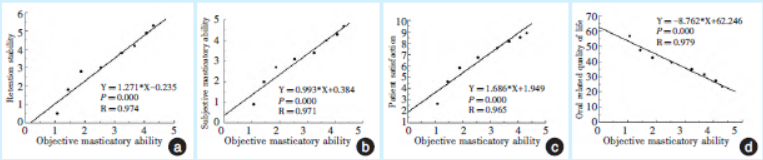

2.6线性相关性结果

以客观咀嚼能力为自变量(X)分别与固位稳定、主观咀嚼能力、义齿满意度、OHIP-14进行相关性分析,结果表明:客观咀嚼能力与义齿的固位稳定性、主观咀嚼能力、义齿满意度呈高度正相关;而与OHIP-14呈高度负相关(图7)。

图7 客观咀嚼能力与固位稳定、主观咀嚼能力、患者满意度及口腔相关生活质量的线性相关性直线图